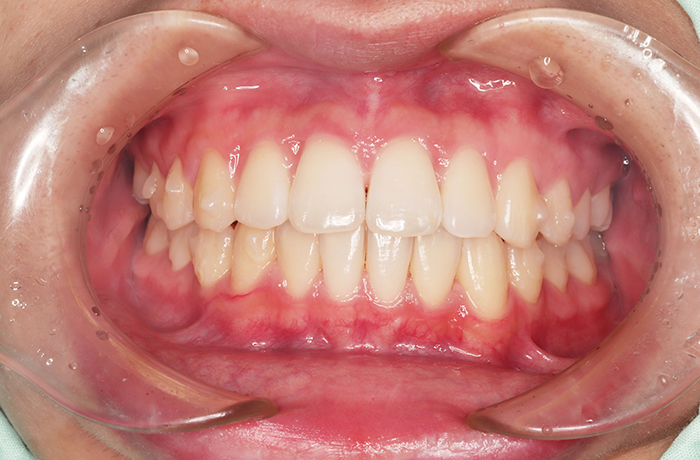

治療前

before

患者の症状 上顎前歯の前突、八重歯

治療方法 上下左右の第一小臼歯抜歯で、マウスピース型カスタムメイド矯正歯科装置による矯正

治療結果 上顎前歯の前突、八重歯が改善されました。

歯並びをより良くするために追加でアライナーを発注しました。